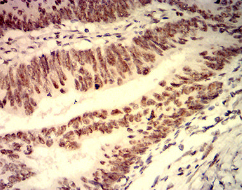

IHC    1/200 - 1/1000